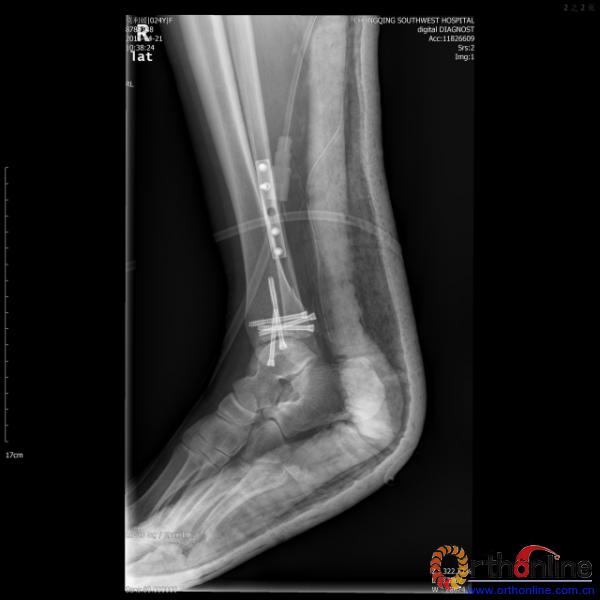

伤员和家属迅速赶到西南医院,10点关节外科段小军副教授查看伤员后急诊收入院,拍摄X片和急诊行三维CT重建检查,提示踝关节创伤严重,出现三踝骨折伴胫距关节脱位,需要急诊手术治疗。随后段教授与正在四川成都参加“汶川地震5周年灾害医学救治研讨会”的杨柳主任联系,进一步完善救治方案。地震当晚,段教授为该伤员进行急诊手术,手术顺利对复杂骨折进行了解剖复位,有效的钢板螺钉固定。术后伤员的疼痛明显缓解,复查X片,踝关节结构恢复满意。

患者术后X片(一)

患者术后X片(二)